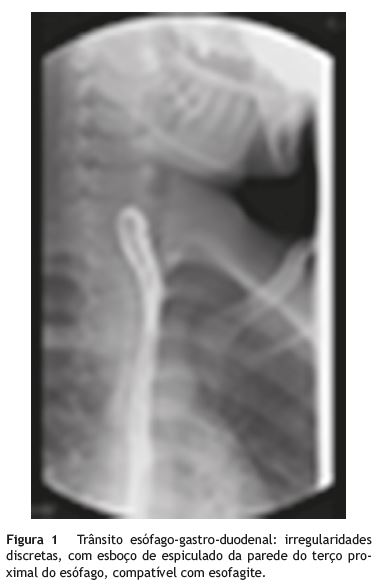

Em janeiro de 2012 realizou trânsito esófago-gastro-duodenal que revelou irregularidades discretas, com esboço de espiculado da parede do terço proximal do esófago compatível com esofagite (fig. 1).